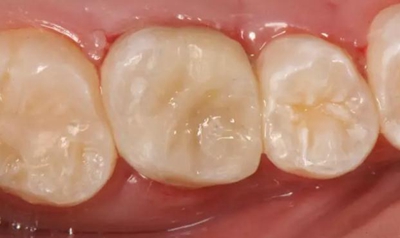

改良垂直褥式縫合關(guān)閉傷口,傷口無(wú)明顯滲血,高嵌體預(yù)備完畢后,硅橡膠取模,見邊緣清晰。灌注模型,模型上3MZ350XT分層堆塑高嵌體。

一周后拆除縫線,試戴高嵌體,試戴合適后雙固化粘結(jié)。調(diào)合,拋光。